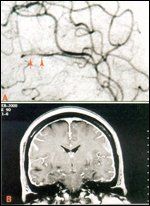

FIGURE 1

Vasculitis vs Metastasis

Leptomeningeal metastases frequently coexist with intraparenchymal brain metastases. The signs and symptoms of the intraparenchymal metastases, including seizures, hemiparesis, and aphasias, may add to the symptoms and signs of leptomeningeal disease and present a confusing picture. In addition, leptomeningeal metastases may narrow pial arteries and lead to stroke or focal hemispheric or brain stem deficits on a vascular basis. Leptomeningeal metastases may produce clinical and arteriographic findings similar to central nervous system (CNS) vasculitis (Figure 1).